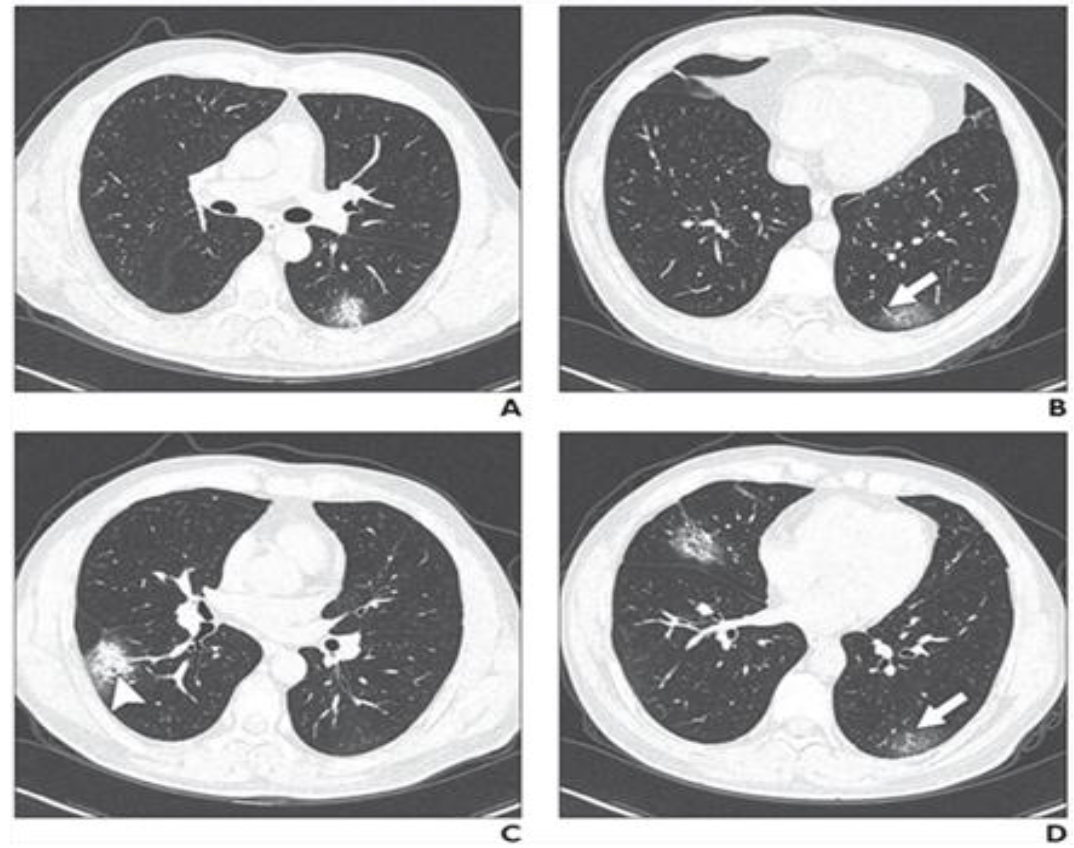

• CT thorax (Figure 1)

Figure 1: Some possible CT findings in Covid-19 lung infection.

Source: Wei Zhao et al, American Journal of Roentgenology: 1–6. 10.2214/AJR.20.22976